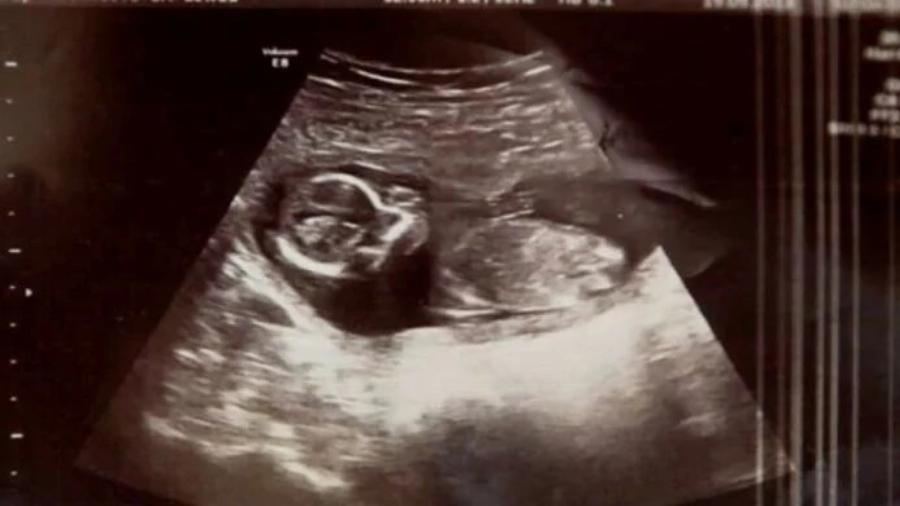

Οι γιατροί στο νοσοκομείο ελέγχουν με υπέρηχο την κοιλιά της Μισέλ για μια τελευταία φορά πριν προχωρήσουν σε ξύσμα της μήτρας και βρίσκουν το αλάνθαστο κτύπο της καρδιάς ενός εμβρύου! Η Μισέλ είναι έγκυος, παρά την αποβολή και την άμβλωση. Αποδεικνύεται ότι ήταν αρχικά έγκυος με δίδυμα, αλλά μόνο ο ένας απεβλήθη. Πώς το δεύτερο μωρό κατάφερε να επιβιώσει, ακόμα και οι γιατροί δεν μπορούν να εξηγήσουν!

“Ο γιατρός βγήκε και επέστρεψε πάλι με ένα μεγαλύτερο σε ηλικία συνάδελφο, ο οποίος επανέλαβε τη διαδικασία και, στη συνέχεια, είπε, “Δεν θα μας πιστέψετε, αλλά έχουμε έναν κτύπο καρδιάς.” Αυτό ήταν το καλύτερο συναίσθημα που είχα ποτέ , λέει η Μισέλ. Στο τέλος, το μωρό Μέγκαν γεννήθηκε υγιέστατο και άφησε άναυδους τους γιατρούς και τους γονείς.

Δεν είναι σαφές, αν υπήρξε ποτέ μια παρόμοια περίπτωση, όπως της Μέγκαν. Σήμερα το μωρό είναι 18 μηνών και είναι απολύτως υγιής. Ακόμη και τα αδέλφια της 4 και 2 χρονών είναι ευτυχισμένα που την έχουν στη ζωή τους. Είναι επίσης άγνωστο το πώς το έμβρυο αγνοήθηκε κατά τη διάρκεια των προηγούμενων εξετάσεων. Οι γιατροί λένε ότι η Μέγκαν ήταν κρυμμένη από τον υπερήχο από το αίμα και άλλα υγρά της αποβολής.